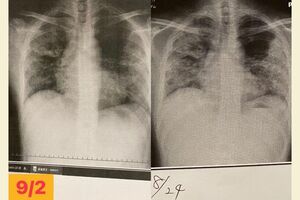

瀬川達也さん(仮名・37歳)はこの夏、コロナに感染し、医師に「死ぬかもしれない」と宣告を受けた。基礎疾患もなく、大きな病気をしたこともない男性だ。至って元気だったが、コロナ感染後に重症化。入院前には血中酸素飽和度が「72%」という極めて危険な数値にもかかわらず、苦しさの自覚症状がない「ハッピー・ハイポキシア」の状態に陥った。さらに三度の入院に至るまでの経緯を、日にちを追って詳しく聞いた。